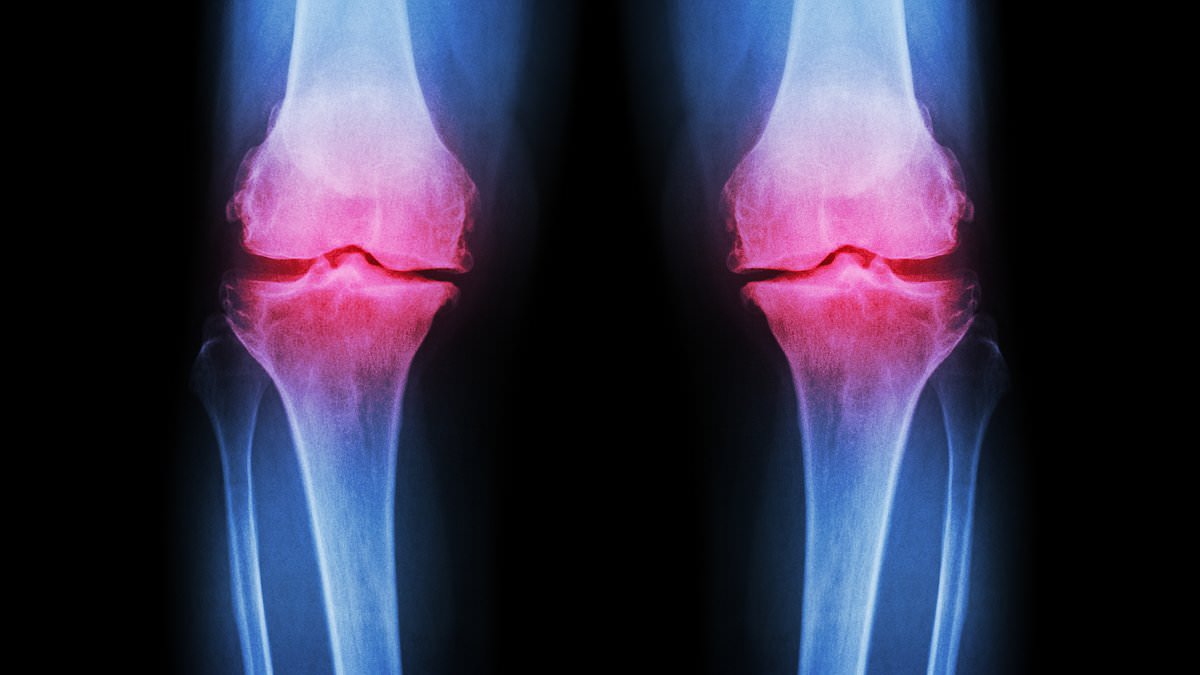

While exercise is widely recognized as one of the most effective defenses against osteoarthritis—a debilitating condition that causes joint pain and stiffness—there is a pressing need to educate the younger demographic about the importance of balanced nutrition and proper resistance training. Without this awareness, they risk sustaining cartilage damage and soft tissue injuries, which are becoming increasingly prevalent in younger patients.

Tim Sinnett, a prominent trauma and orthopaedic consultant, highlights a worrying trend: “We are seeing younger and younger patients presenting with more advanced cartilage damage. The assumption is that these are the results of extreme and intense exercise regimes.” As such, a more informed approach to fitness, incorporating a balance of exercise types and dietary habits, is crucial to safeguarding the health and well-being of future generations.

‘We are seeing younger and younger patients presenting with more advanced cartilage damage, and the presumption there is that they’re picking up more soft tissue injuries around the joint, as a result of more extreme and more intense exercise,’ explained Tim Sinnett, a leading trauma and orthopaedic consultant.

By the age of 70, around half of people will develop arthritis, but some are affected much younger. Osteoarthritis, which affects around 10 million people in the UK, is the most common type of the condition, and is increasingly being diagnosed in the younger generations.

But in osteoarthritis, the protective cartilage on the ends of bones breaks down until the joints are no longer able to fully repair themselves.

A range of factors is thought to cause this increase in cartilage degradation, including genetics, obesity, repeated stress on joints, age, smoking and injury.

Post-traumatic osteoarthritis is related to fractures that extend into a joint such as the ankle, wrist and knee.

These can cause improper healing which alters joint mechanics and leads to cartilage breaking down more rapidly.

Osteoarthritis develops when the cartilage that cushions joints breaks down over time. Cartilage normally acts as a shock absorber, allowing bones to move smoothly.

As it wears away, joints lose this protection and bones eventually rub together, resulting in swelling, tenderness, and grating when moving the affected joints.

The severity of the condition can vary, and usually takes years to develop. Early symptoms such as mild knee or hip pain or stiffness that comes and goes are often dismissed as a sign of needing to exercise more.